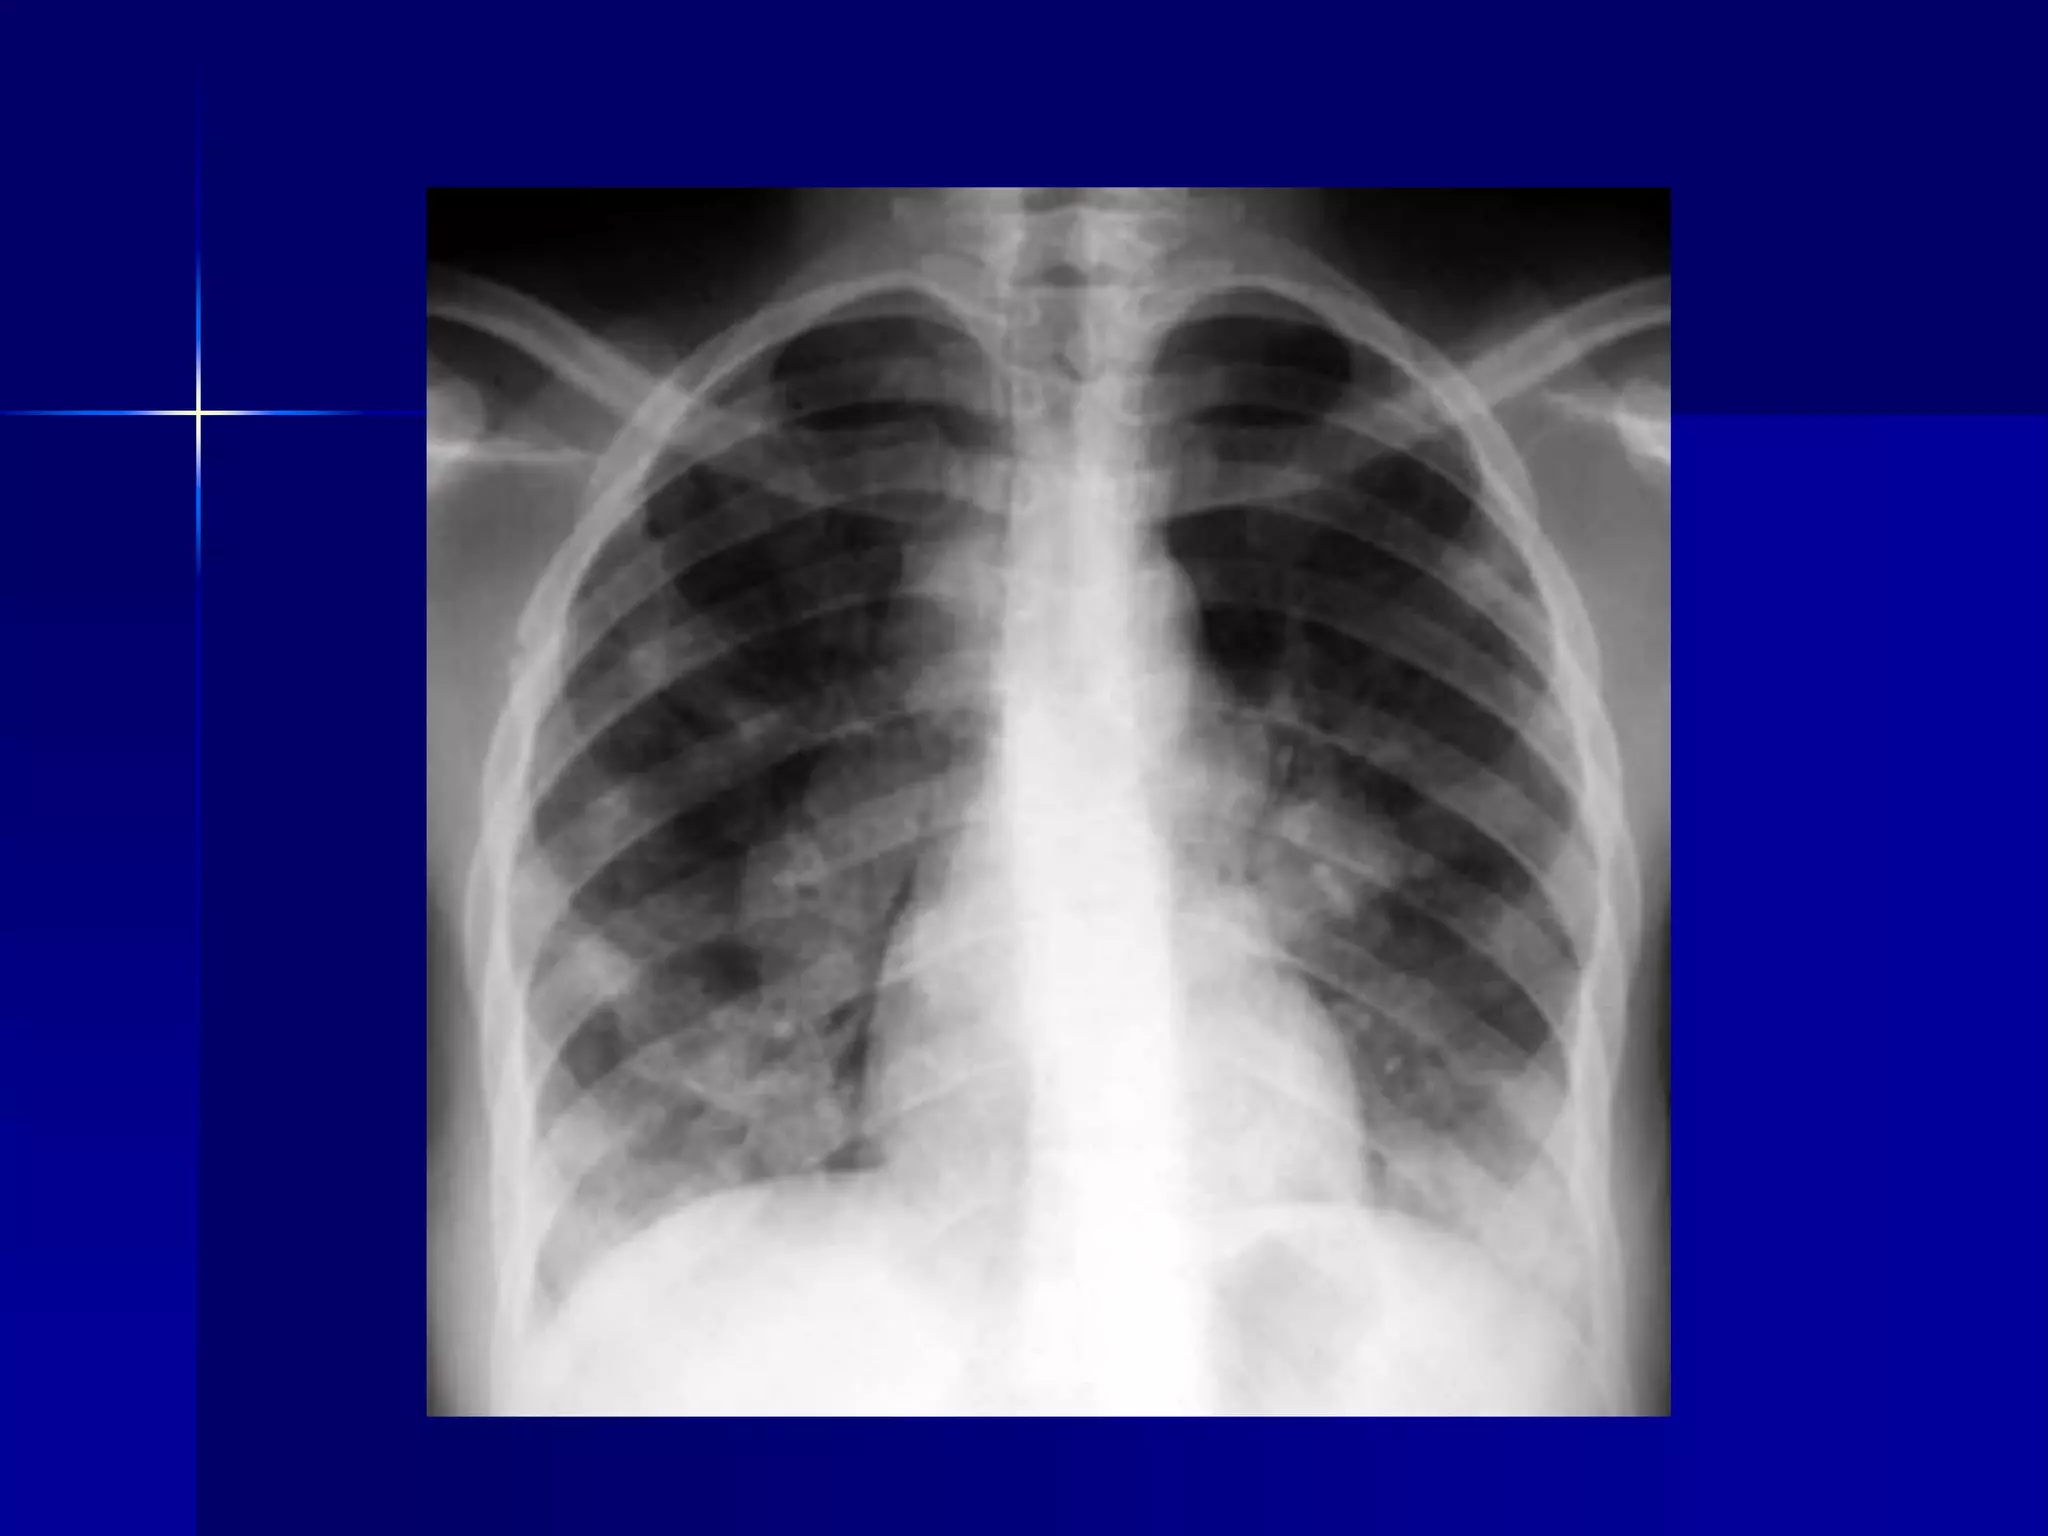

Atelectasis Left Lung

 Homogenous density left hemithorax

 Mediastinal shift to the left

 Diaphragmatic and heart silhouette

are not identifiable